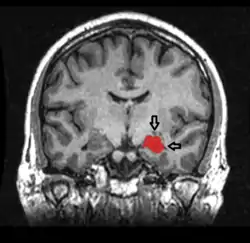

![]() Магнітно-резонансна томографія. На зінмку зображені структури головного мозку включаючи гіпокапм (виділений червоним кольором). | |